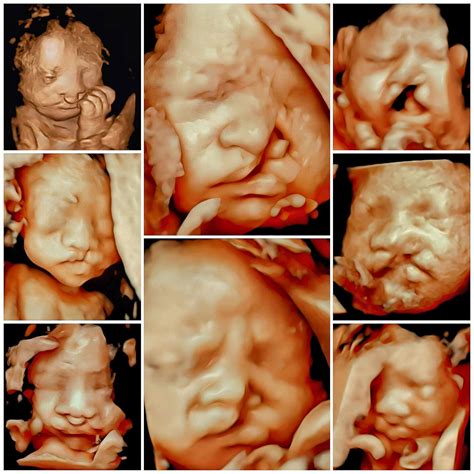

14W Fetus Face 3D

The 14th week of pregnancy is a crucial stage in fetal development. By this point, the fetus has undergone significant changes, and many of its features are becoming more defined. The baby's face, in particular, starts to take shape, with the eyes moving closer together and the ears becoming more prominent. The 14W fetus face 3D imaging technology captures these details with remarkable clarity, providing a detailed view of the baby's facial features.

Interpreting 3D ultrasound images requires specialized training and expertise. Healthcare providers are trained to identify normal and abnormal features in the images. For a 14W fetus face 3D image, they will look for specific markers of development, such as:

• Facial Symmetry: Ensuring that the baby's facial features are symmetrical and proportionate.

• Eye and Ear Position: Checking the position and development of the eyes and ears.

• Nose and Mouth: Assessing the formation of the nose and mouth, including the presence of a cleft lip or palate.

• Overall Facial Structure: Evaluating the overall structure and appearance of the face for any signs of abnormalities.